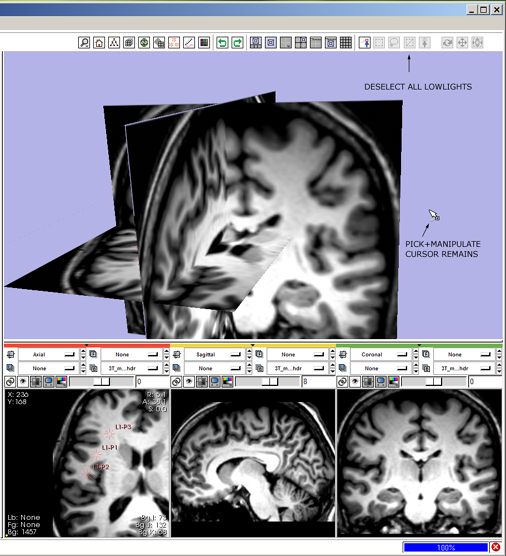

| + | 9(novice) '''move multiple fiducials:''' click the mouse-pick-and-manipulate icon [[image:ToolbarMouseManipulate.png]] | ||

* --> mouse-pick-and-manipulate icon highlights, all others deselect, cursor changes to indicate mouse-pick-and-manipulate mode. | * --> mouse-pick-and-manipulate icon highlights, all others deselect, cursor changes to indicate mouse-pick-and-manipulate mode. | ||

* left-Click and drag in a Slice Viewer to reposition the fiducial points. | * left-Click and drag in a Slice Viewer to reposition the fiducial points. | ||

| − | + | 9(expert) '''move multiple fiducials:''' press 1-key to switch into mouse-pick-and-manipulate mode. | |

| − | + | * --> mouse pick-and-manipulate icon [[image:ToolbarMouseManipulate.png]] highlights, and all others deselect; cursor changes to indicate mouse-pick-and-manipulate mode, | |

| + | * left-Click and drag in the Slice Viewer to reposition multiple fiducials. | ||

| − | + | [[image:SB9.png]] | |

| − | + | 10(novice) '''de-select fiducials:''' click the mouse-deselect-all icon [[image:ToolbarMouseDeselectAll.png]] | |

| − | + | * --> mouse-deselect icon hightlights, all other icons deselect, and the fiducials are deselected. | |

| − | + | 10(expert) '''de-select fiducials:''' press 4-key again to deselect the fiducial points | |

| − | |||

9(novice) move multiple fiducials: click the mouse-pick-and-manipulate icon ![]()

- --> mouse-pick-and-manipulate icon highlights, all others deselect, cursor changes to indicate mouse-pick-and-manipulate mode.

- left-Click and drag in a Slice Viewer to reposition the fiducial points.

9(expert) move multiple fiducials: press 1-key to switch into mouse-pick-and-manipulate mode.

- --> mouse pick-and-manipulate icon

highlights, and all others deselect; cursor changes to indicate mouse-pick-and-manipulate mode,

highlights, and all others deselect; cursor changes to indicate mouse-pick-and-manipulate mode, - left-Click and drag in the Slice Viewer to reposition multiple fiducials.

10(novice) de-select fiducials: click the mouse-deselect-all icon ![]()

- --> mouse-deselect icon hightlights, all other icons deselect, and the fiducials are deselected.

10(expert) de-select fiducials: press 4-key again to deselect the fiducial points

- --> the deselect-all icon

highlights and all other icons are deselected, the fiducial is no longer highlighted.

highlights and all other icons are deselected, the fiducial is no longer highlighted.